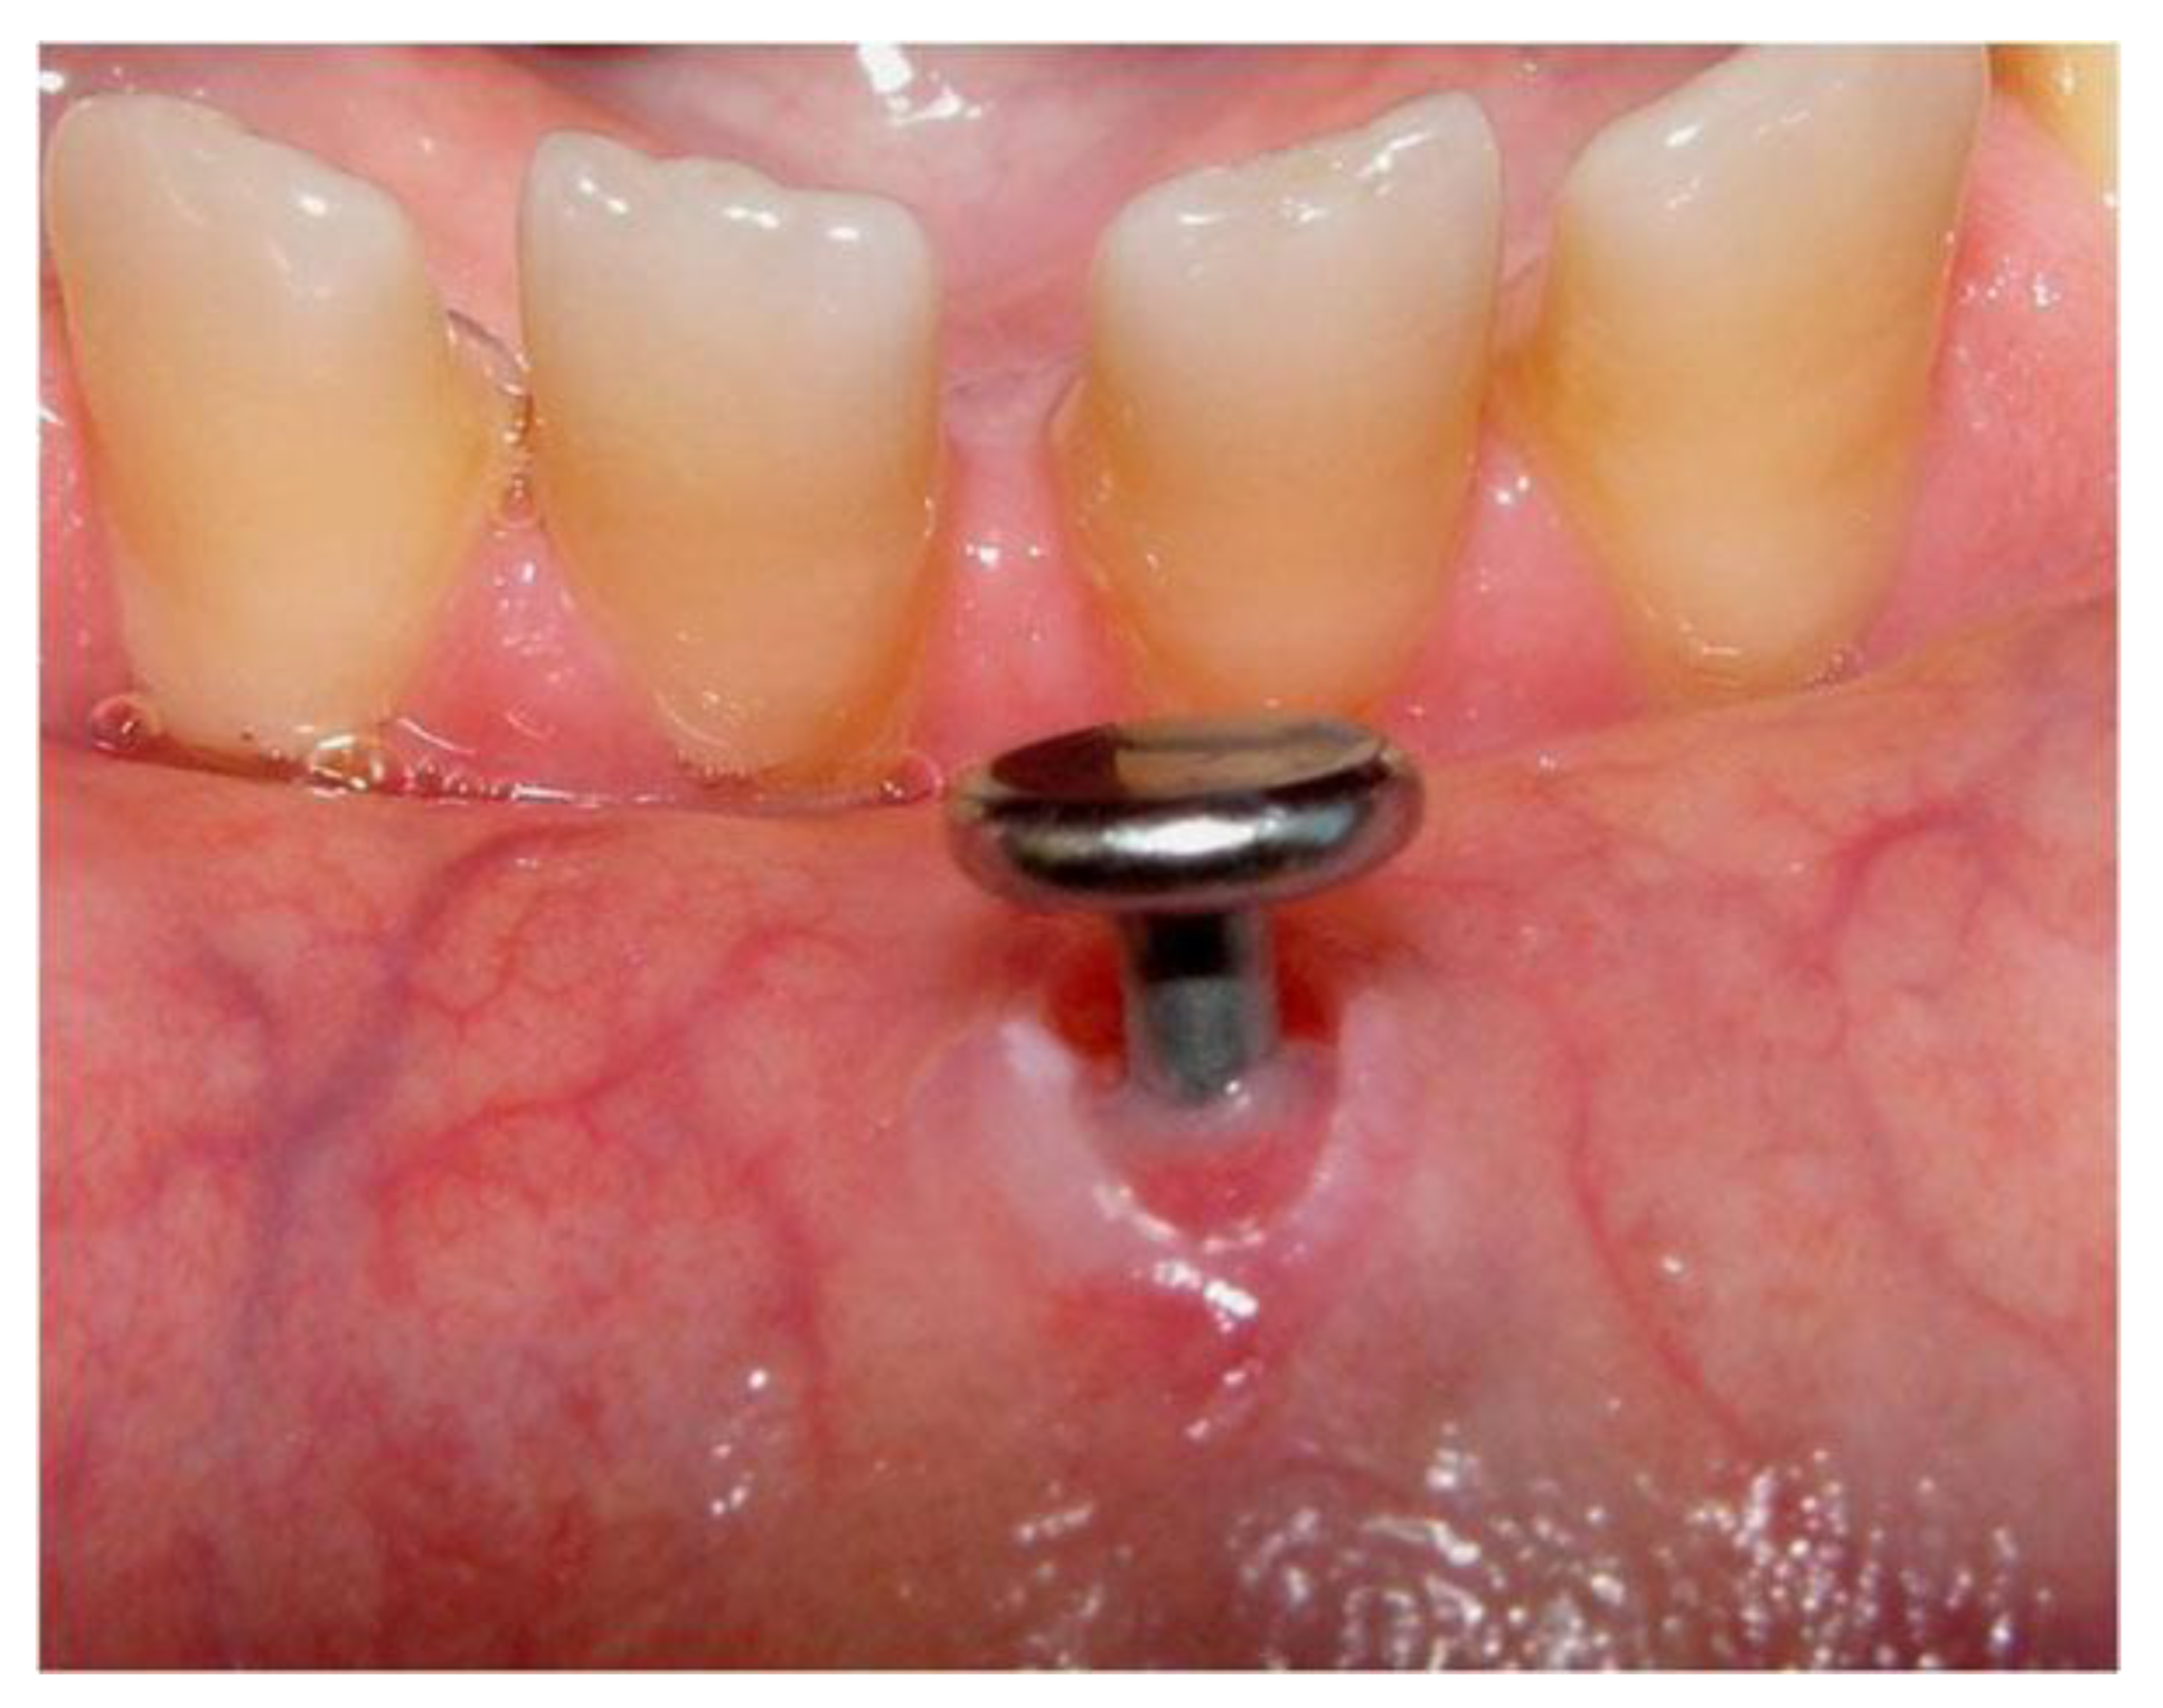

Figure 3.

Mucosal damage around a labial piercing [53].